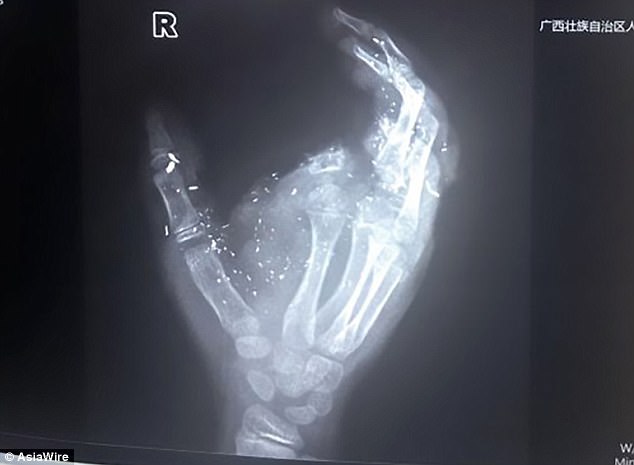

Ένα κινεζικό κινητό τηλέφωνο που εξερράγη, ενώ το κρατούσε, είχε ως αποτέλεσμα ένα 12χρονο αγόρι από την Κίνα να χάσει το μάτι και ένα δάκτυλό του.

Τοπικά ΜΜΕ αναφέρουν ότι το αγόρι τραυματίστηκε σοβαρά και χρειάστηκε να υποβληθεί σε 5ωρη χειρουργική επέμβαση όταν το κινητό τηλέφωνο μάρκας Hua Tang VT-V59 εξερράγη στα χέρια του.